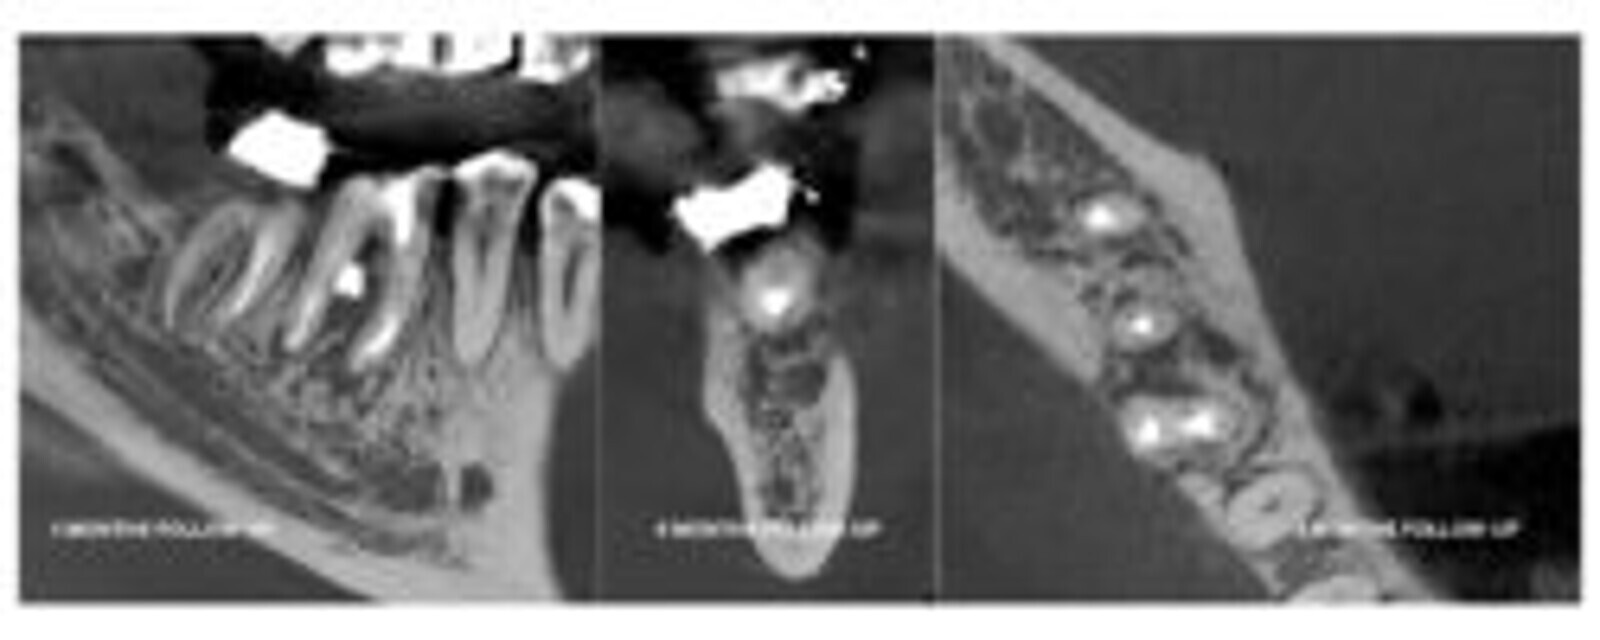

Nakon 4 meseca pacijent je pozvan na kontrolu. CBCT pregled je pokazao da je došlo do procesa zaceljivanja i da je kost ponovo izgrađena.

SLIKA 7